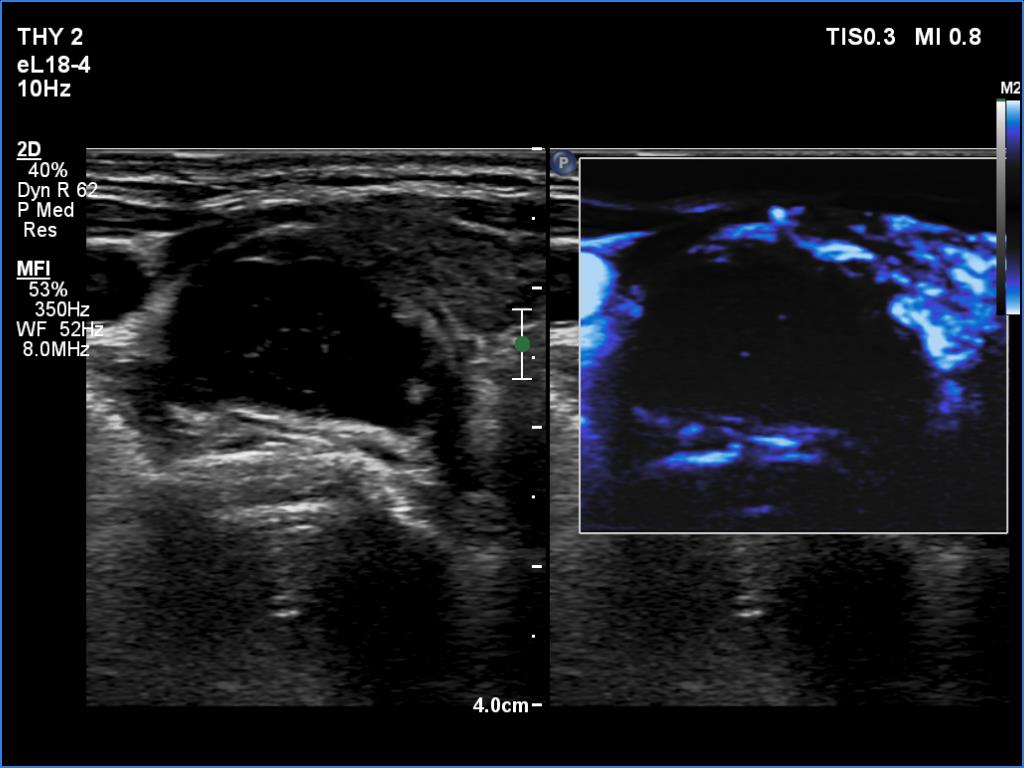

Ultrasonography. The thyroid was hypoechoic and presented several more hypoechoic and echonormal islets corresponding to the underlying thyroiditis. There was a mixed, dominantly cystic mass dorsal to the lower two-third of the right lobe. The lesion has echonormal solid part and showed intracystic echogenic figures.